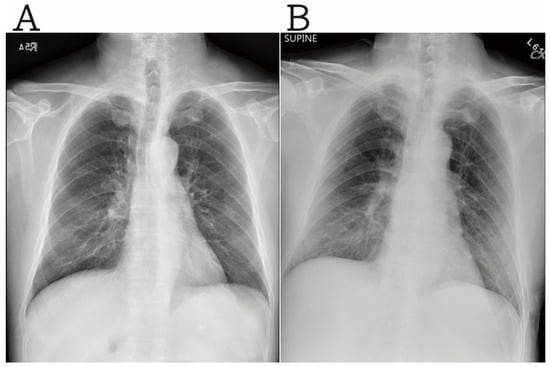

2. Case Presentation